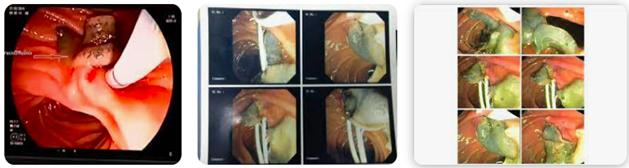

Hình 9. Phối hợp Siêu âm, CT-scan và thủ thuật ERCP trong điều trị sán lá gan lớn ở mật-tụy

Thông thường soi ổ bụng cho thấy các u, nốt màu trắng xám hay vàng, kích thước 2-20mm và có các bề mặt dạng dây xơ hóa. Một số ca hiếm hơn có thể gặp dạng nốt ở khắp khoang phúc mạc và thành ruột. Phẩu thuật ổ bụng thăm dòcó thể phát hiện SLGL và trứng sán trong ổ bụng hoặc đường mật. Các thủ thuật cận lâm sàng khác hiếm khi áp dụng trong chẩn đoán bệnh SLGL như nội soi đường tiêu hóa trên vì thường nhiễm SLGL có thể gây hội chứng viêm tiêu hóa tăng bạch cầu ái toan (nhằm phân biệt giữa loét dạ dày tá tràng), nội soi có thể thấy tổn thương lấp đầy trong hệ đường mật và túi mật; nếu được thì chúng ta có thể loại bỏ sán thông qua nội soi.

Nhiều trường hợp áp dụng ERCP và các can thiệp khacshuts cả dịch tá tràng, một ít dịch mật xét nghiệm thấy trứng sán bên trong

Hình 10. Áp dụng nhiều thủ thuật vừa giúp chẩn đoán, vừa điều trị cabệnh nội-ngoại khoa